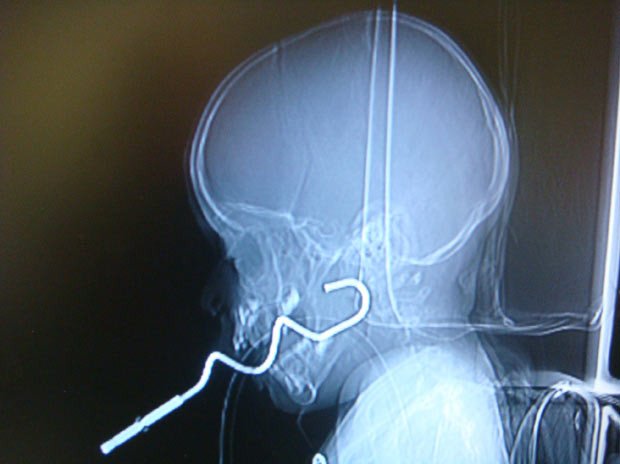

| Cậu bé đang điều trị tại bệnh viện Bo Ai ở Bắc Kinh, Trung Quốc do không may ngã vào một chiếc que |

| Phim X-quang về một cậu bé 3 tuổi bị dụng cụ trộn thức ăn xuyên vào đầu. Cậu bé đang chạy ở một nhà trẻ ở Israel cùng với dụng cụ này thì bị ngã. Các bác sĩ đã lấy được nó ra một cách an toàn |